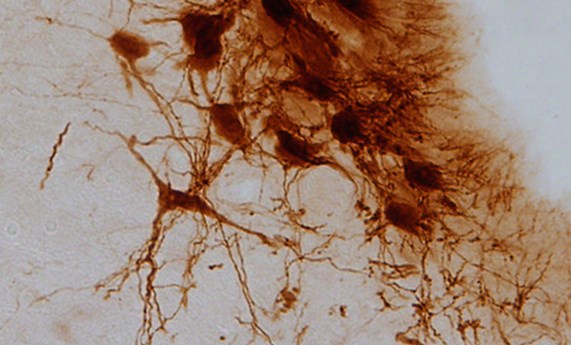

Moléculas reguladas con luz para aliviar síntomas del dolor crónico